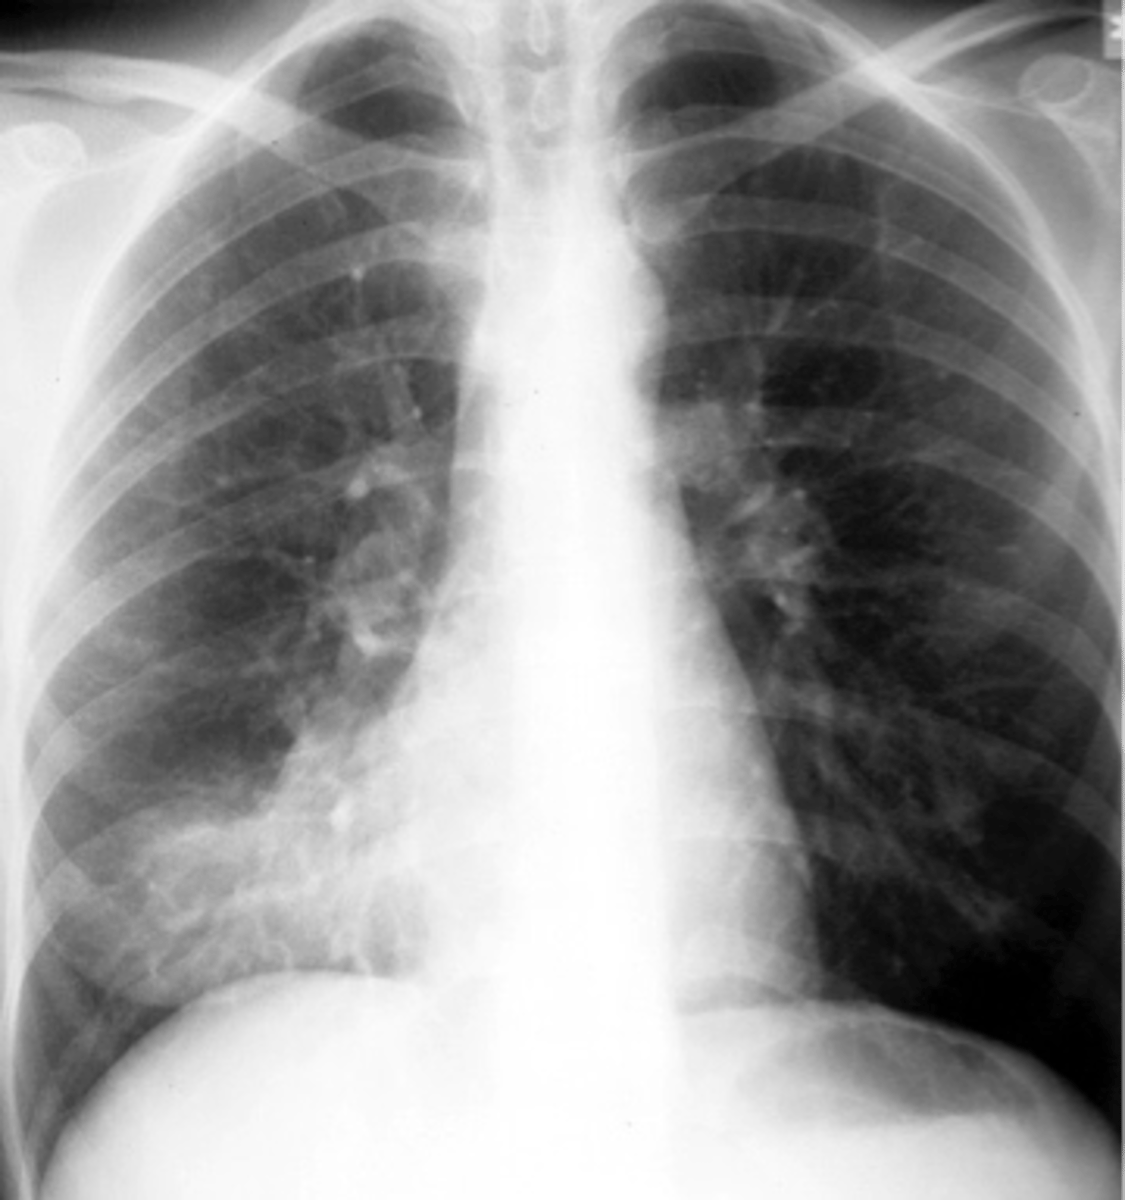

Bilateral interstitial infiltrates